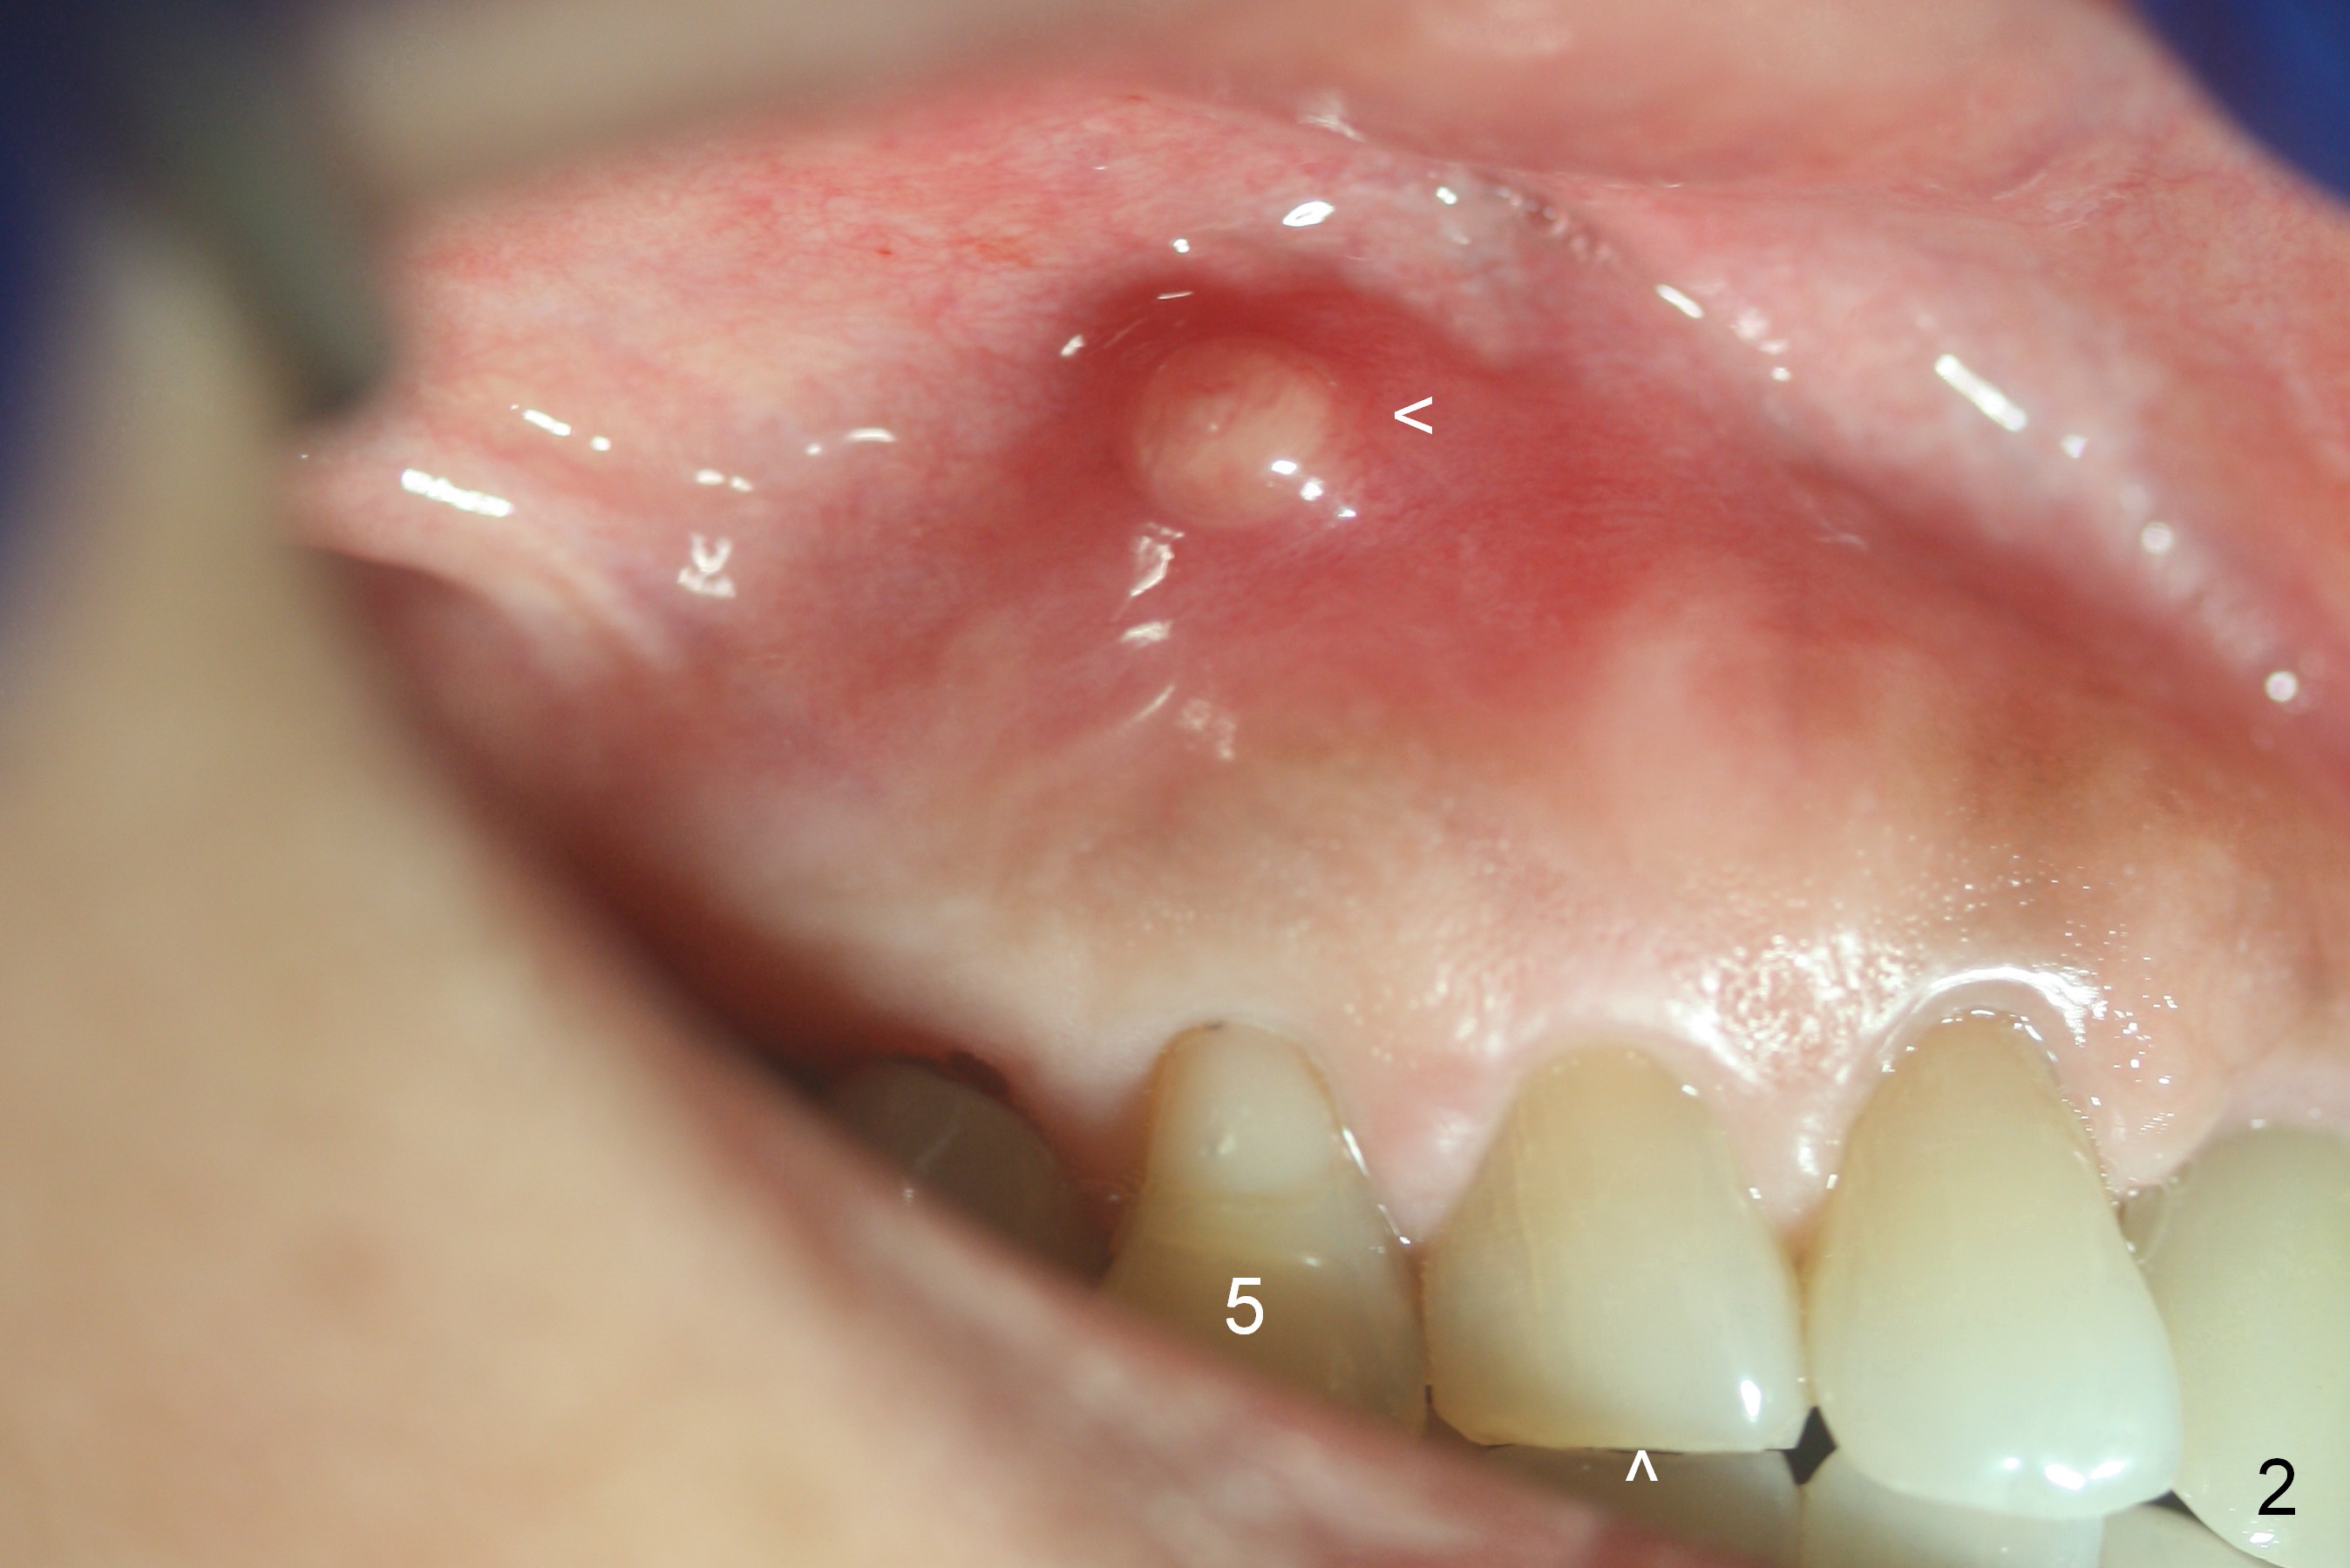

A 72-year-old lady is a bruxer with palatal subgingival fracture of the upper right 1st premolar (Fig.1) with a fistula/periapical radiolucency (Fig.2,3 <). She insists on saving the tooth, since it is asymptomatic. Bruxism must be severe, as the canine (Fig.2 ^) is shorter than the lateral incisor. She has history of #8 fracture and loosening of implant crown at #14.

After long discussion, she agrees with extraction and immediate implant. After the extraction, granulation tissue is removed. There is buccal apical fenestration. The socket is treated with Metronidazole. The socket depth is 17 mm, while osteotomy depth is 20 mm (Fig.4). A 4x20 mm tissue-level implant is placed with primary stability (Fig.5,6 I). A short abutment (A) is placed immediately for an immediate provisional. The buccal gap is filled with Osteogen plug. There is no crestal bone loss 3 months postop (Fig.7). The provisional stays in place with occlusal perforation. The gingiva is healthy 5.5 months post cementation (Fig.8).